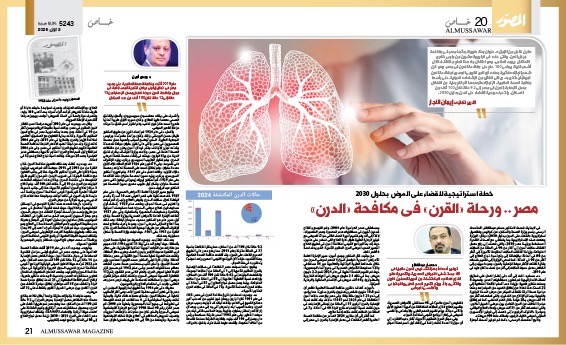

«قرن كامل من الزمان»، عنوان رحلة طويلة بدأتها مصر فى مكافحة مرض الدرن، والتى حلت فى الرابع والعشرين من مارس ذكرى الاحتفال بيومه العالمى، وهو احتفال جاء هذا العام مختلفًا، فخلال أشهر قليلة يمضى100 عام على مكافحة الدرن فى مصر، وهو قرن شهد إنجازات كثيرة جعلت البرنامج القومى المصرى لمكافحة الدرن نموذجًا يُحتذى به، ويلقى الكثير من الإشادات الدولية، على رأسها منظمة الصحة العالمية، الإنجازات ترصدها الأرقام بداية من انخفاض معدل الإصابة بالدرن فى مصر إلى 9.2 حالة لكل 100 ألف من السكان، والتحرك بجدية للقضاء على الدرن بحلول 2030.

فى البداية، تحدث الدكتور حسام عبدالغفار، المتحدث الرسمى باسم وزارة الصحة والسكان، عن كواليس وتفاصيل استراتيجية «القضاء على الدرن بحلول 2030»، وقال: الوزارة وضعت هذه الاستراتيجية بما يتماشى مع أهداف التنمية المستدامة ورؤية مصر 2030، والتى تهدف إلى رفع معدل اكتشاف حالات الدرن إلى أكثر من 90 فى المائة من الحالات المتوقعة، وزيادة اكتشاف الحالات المقاومة للأدوية إلى أكثر من 80 فى المائة، بالإضافة إلى رفع نسبة نجاح العلاج إلى أكثر من 90 فى المائة، كما تسعى الوزارة إلى تقديم خدمات وقائية للفئات الأكثر عرضة للإصابة بالدرن، وهو ما سيؤدى إلى انخفاض معدل حدوث الحالات إلى أقل من نصف ما كان عليه فى عام 2015.

«أمين»، أضاف: «تقارير منظمة الصحة العالمية تظهر أن نحو 10.8 مليون شخص يُصابون بالدرن سنويًا، مما يؤدى إلى نحو 1.25 مليون حالة وفاة، وفى مصر بلغ عدد حالات الدرن المكتشفة فى عام 2024 نحو 11007 حالات، وقد كانت نسبة الإصابة بالدرن الرئوى 53 فى المائة من إجمالى الإصابات، فى حين كانت نسبة الإصابات خارج الرئة 40 فى المائة، و7 فى المائة من الحالات كانت حالات إعادة علاج».

كما أشار إلى أن «تقرير 2024 الصادر عن منظمة الصحة العالمية أظهر انخفاضًا فى معدل الإصابة بالدرن فى مصر إلى 9.2 حالة لكل 100 ألف من السكان، مما يمثل انخفاضًا بنسبة 37 فى المائة مقارنة بعام 2015، مما يضع مصر على الطريق الصحيح للقضاء على الدرن، وقد أشادت منظمة الصحة العالمية بهذا التقدم»، مؤكدًا أن البرنامج القومى المصرى يُعد نموذجًا يُحتذى به فى هذا المجال.

وتابع: «كما سجلت مصر انخفاضًا فى حالات الإصابة بالدرن المقاوم للأدوية إلى 1 فى المائة من الحالات الجديدة، وانخفضت الوفيات إلى 0.42 حالة لكل 100 ألف من السكان، وارتفعت نسبة التغطية العلاجية إلى 88 فى المائة من الحالات المتوقعة، بينما وصل معدل نجاح العلاج إلى 87 فى المائة فى حالات الدرن الحساسة للأدوية، و75 فى المائة فى حالات الدرن المقاوم للأدوية».